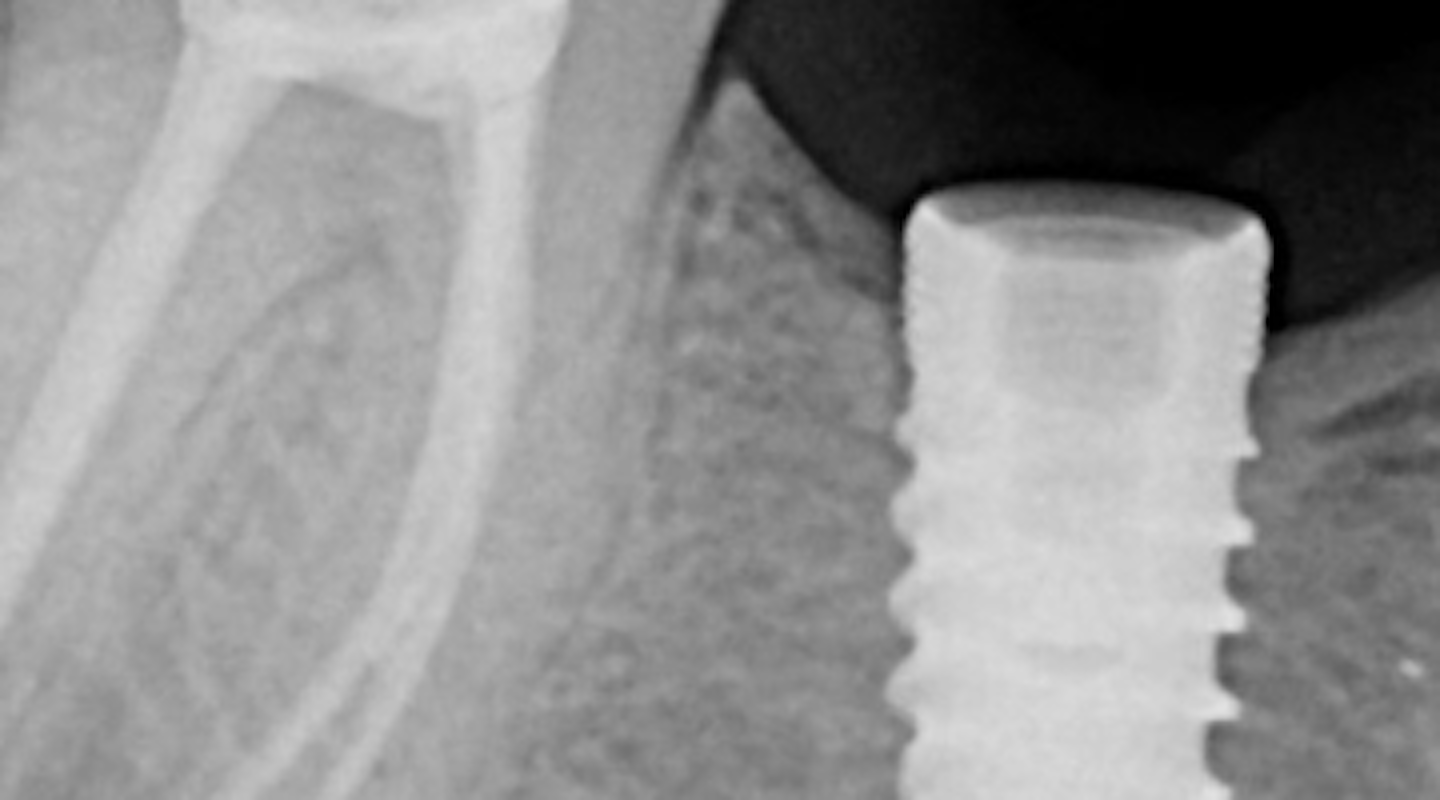

Fractured dental implant screw complications 3 methods for screw